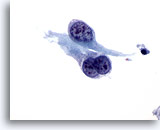

画像 2

肺FNA、肺大細胞癌明瞭な細胞縁を呈するシート状低分化癌細胞。細胞は統制されておらず、局所的に核の重積が見られます。背景には何も見られず、腫瘍性背景を呈していません。腫瘍細胞には、扁平上皮ないし腺管への分化に特異的な特徴は認められません。

40倍

画像 2

肺FNA、肺大細胞癌

明瞭な細胞縁を呈するシート状低分化癌細胞。細胞は統制されておらず、局所的に核の重積が見られます。背景には何も見られず、腫瘍性背景を呈していません。腫瘍細胞には、扁平上皮ないし腺管への分化に特異的な特徴は認められません。

40倍